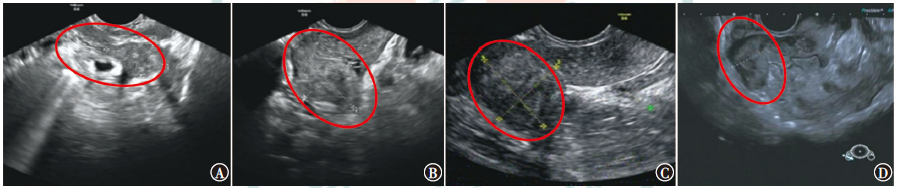

恶性腹膜间皮瘤是原发于腹膜间皮细胞的一种罕见恶性肿瘤,本例恶性腹膜间皮瘤晚期患者,通过特瑞普利单抗联合安罗替尼治疗后,CA125降至正常,病灶评估达到稳定,患者临床获益明显。该治疗方案对提高患者生命质量、稳定病灶起到了一定的作用。